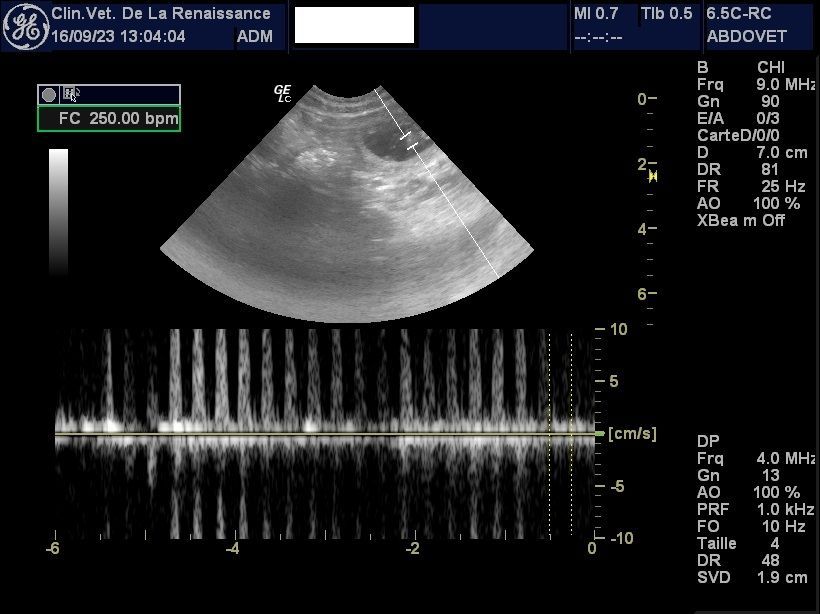

- Confirmation puis surveillance du bon déroulement de la gestation grâce aux examens échographiques.